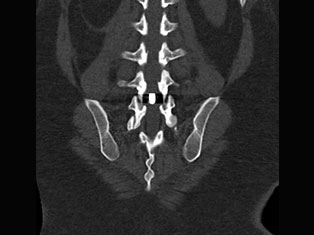

Degenerative Spine

The phrase "degenerative changes" in the spine refers to osteoarthritis of the spine. Osteoarthritis is the most common form of arthritis. Doctors may also refer to it as degenerative arthritis or degenerative joint disease.